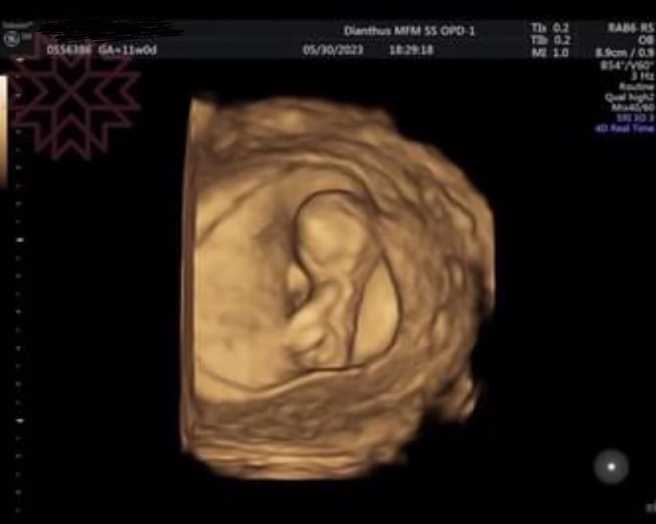

杨绣惠PO超音波照求恭喜。(图/FB@杨绣惠)

眼尖的网友发现,杨绣惠的超音波照的左上角名,是1992年生的柯姓女子,笑说:「左上方有准妈妈的名字」、「老实说:妈妈是谁……」杨绣惠后来把左上角的名字打上马赛克,至今未松口真相。